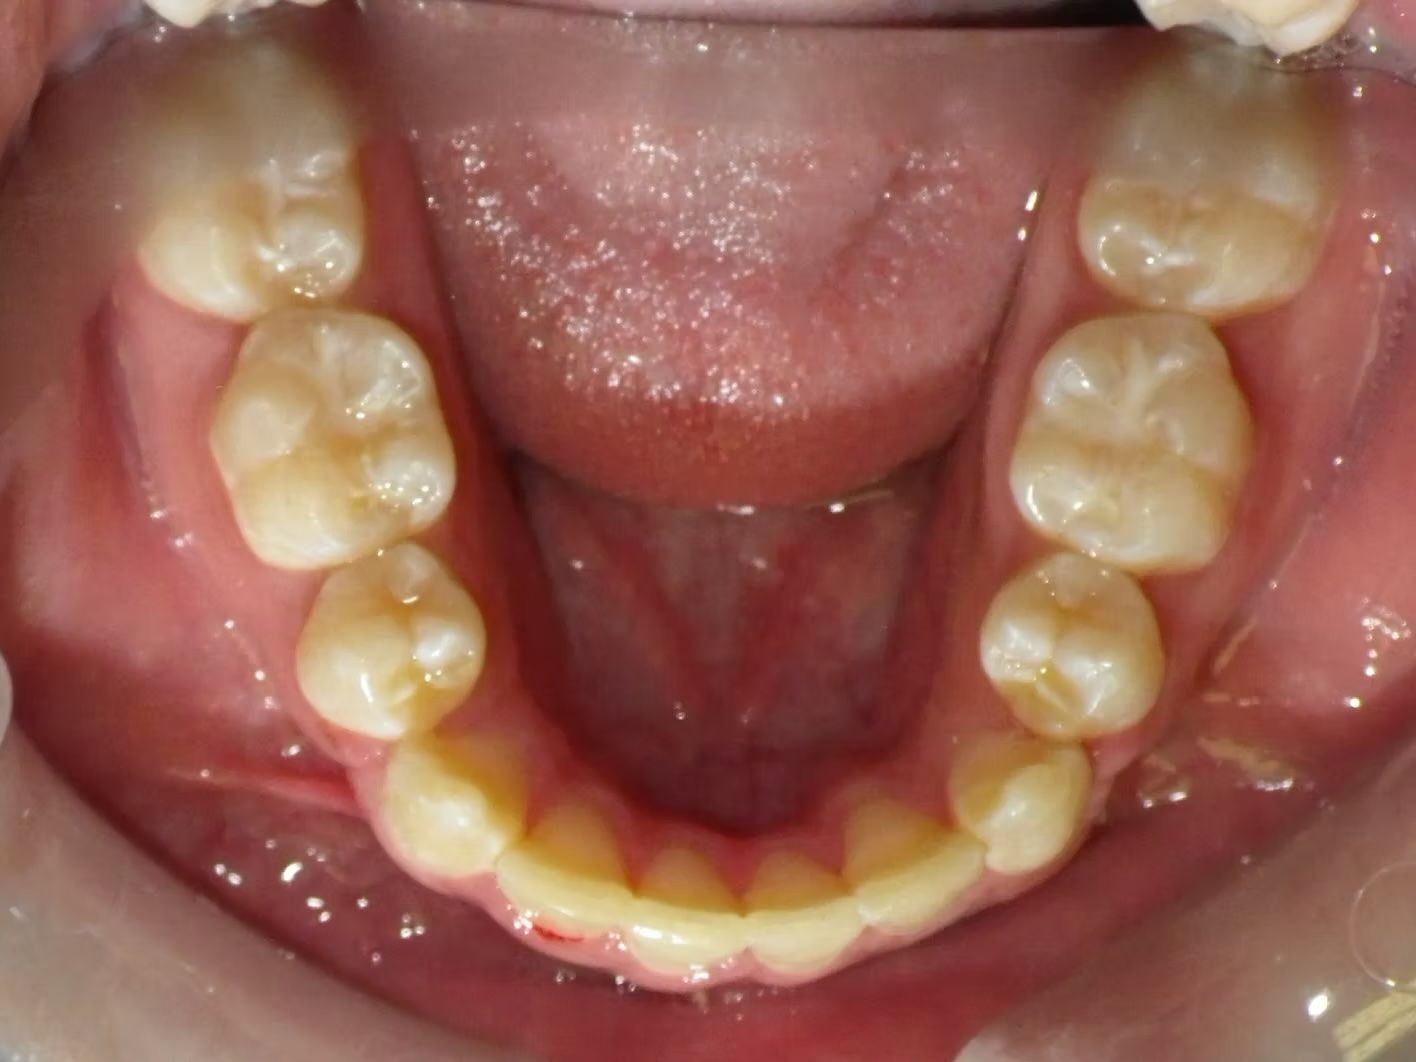

Johntavious

Johntavious didn't like that one of his lower teeth was set behind the rest. He went to many orthodontists who told him to extract the tooth or multiple teeth to correct the alignment. Johntavious and his parents didn't want to go that route and wanted to try to align the teeth without the extraction. Dr. Bret was able to successfully straighten the upper and lower teeth - fit the tooth that was back into the dental arch and make Johntavious and his parents really happy.